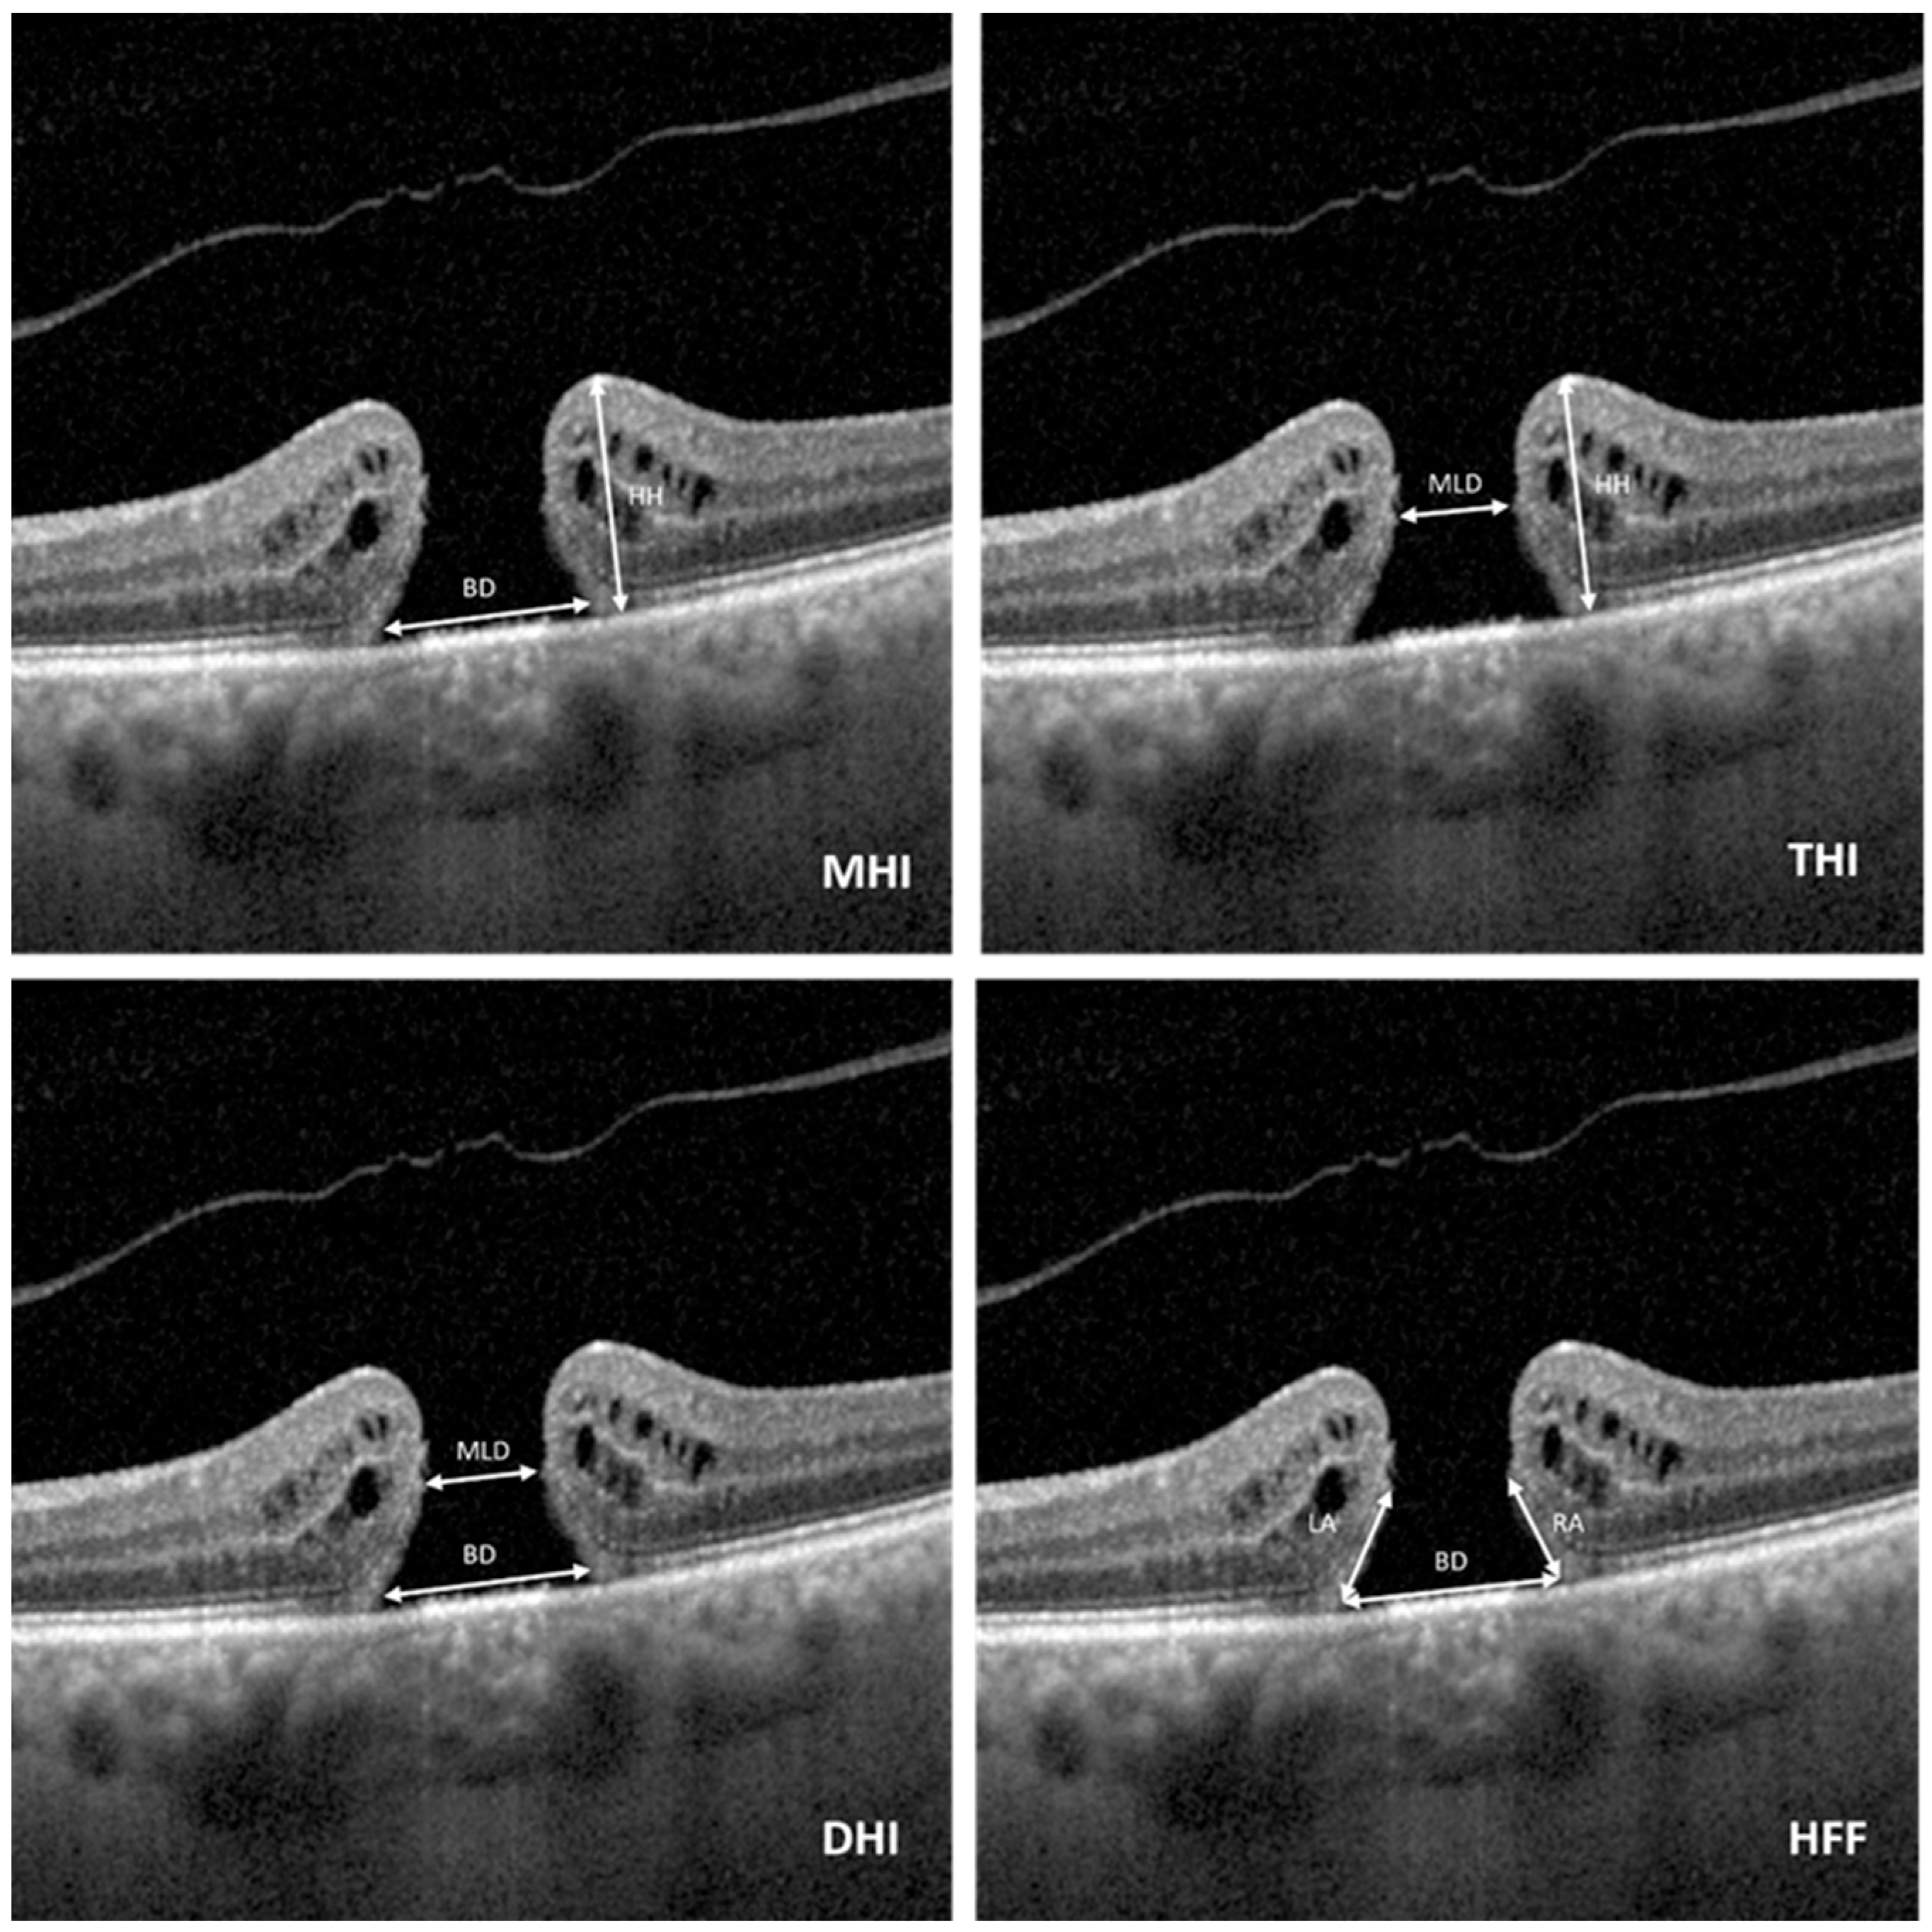

| MHI | 0.51 (0.15) | 0.41 (0.07) | <0.001 |

| THI | 1.31 (0.3) | 0.88 (0.22) | <0.001 |

| DHI | 0.41 (0.13) | 0.47 (0.08) | 0.030 |

| HFF | 0.79 (0.15) | 0.65 (0.12) | <0.001 |